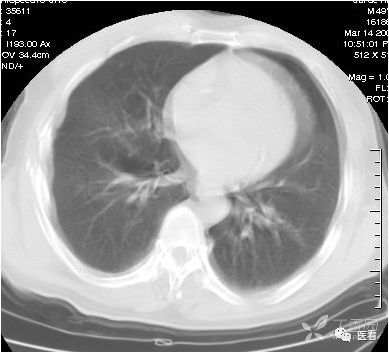

本例为呼吸运动产生的伪影--肋骨呈双边;肺纹理模糊不清。